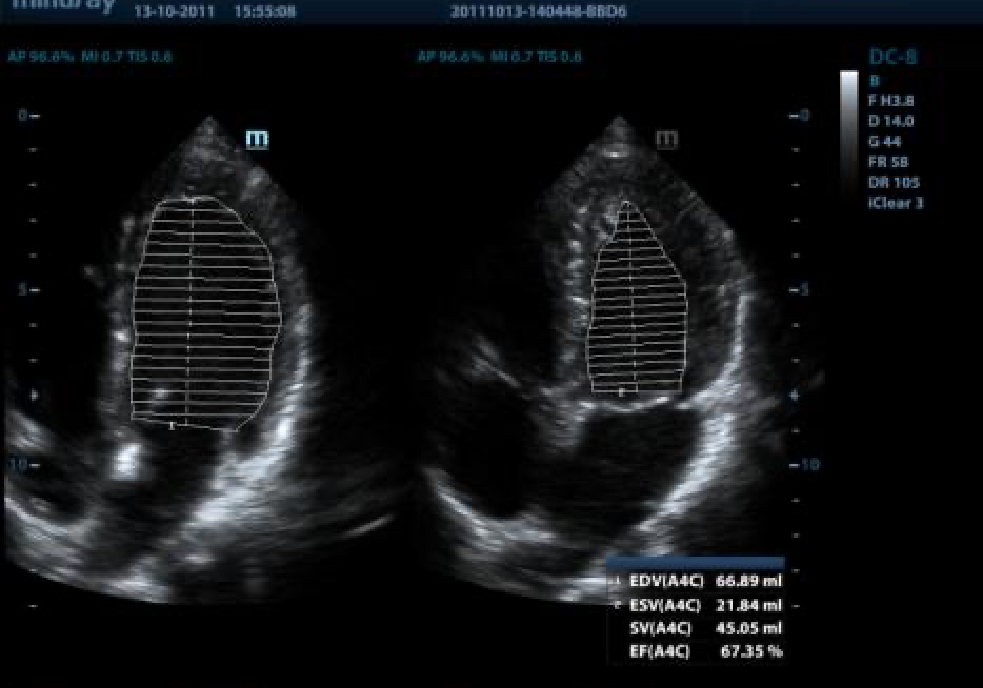

AutoEF

Intelligent way to analyze 2D echo clips to automatically recognize diastole/systole frames and output EDV/ESV/EF etc. results by Simpson method.